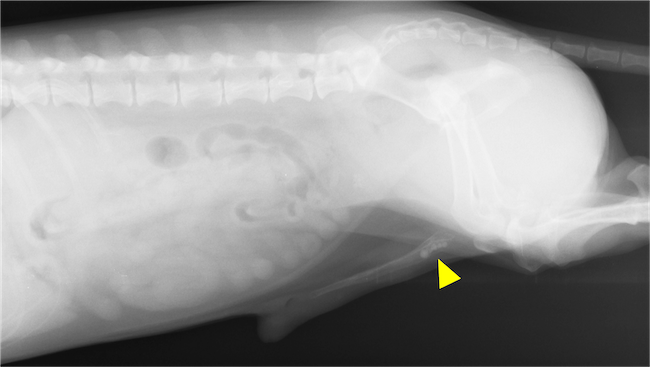

排尿できずに拡張した膀胱